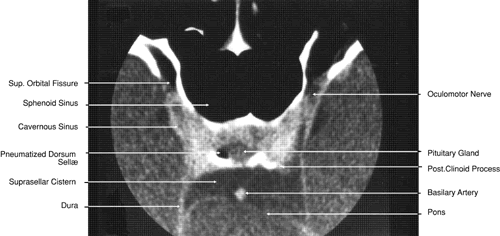

Fig. 28. Axial computed tomography image with contrast medium through cavernous sinus and pituitary gland.